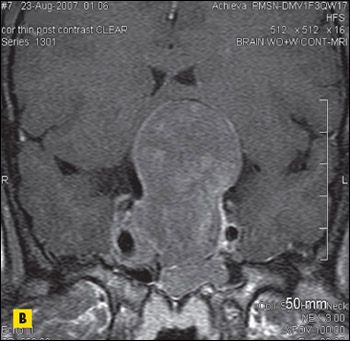

Acromegaly was diagnosed in a 36-year-old woman who presented with loss of vision in the right eye that had initially involved the peripheral field. MRI scans of the brain revealed a 6 × 6 × 4-cm sellar mass with suprasellar and parasellar extension encasing the right cavernous sinus and carotid artery.